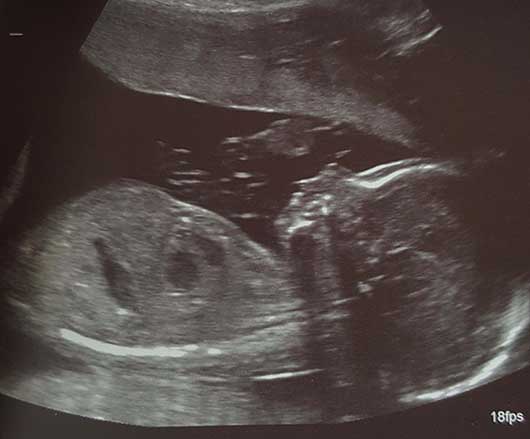

An ultrasound image of |